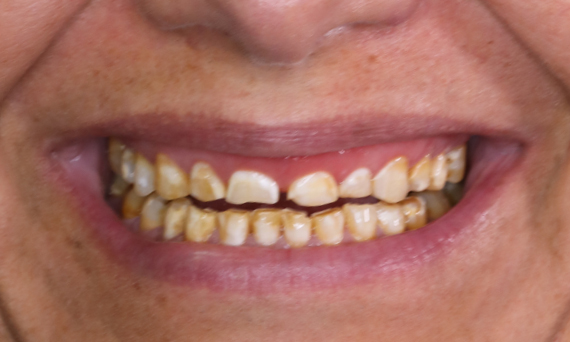

Quadrant rehabilitation in 2 sessions

Ten VITA Suprinity PC single crowns

The patient wanted a beautiful smile. As teeth 15 to 25 are all visible, the decision was made to use a highly esthetic ceramic for all 10 of them. Due to the extensive consultation and the implementation with a mock-up, the restoration was carried out in two sessions with CEREC.

Before: Patient, dissatisfied with her smile due to tooth discoloration.

After: Ten highly esthetic single crowns, individualized with stains.

Dr. Daniel Vasquez

San Diego, USA